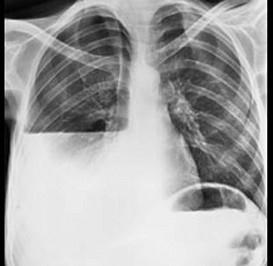

问题 如图,脓胸病人的X胸片出现液气平面,可能有下列哪些原因 ( )

选项 A、膈疝合并肠穿孔 B、以上都是 C、支气管或气管瘘 D、食管穿孔 E、曾经作过胸腔穿刺

答案 B